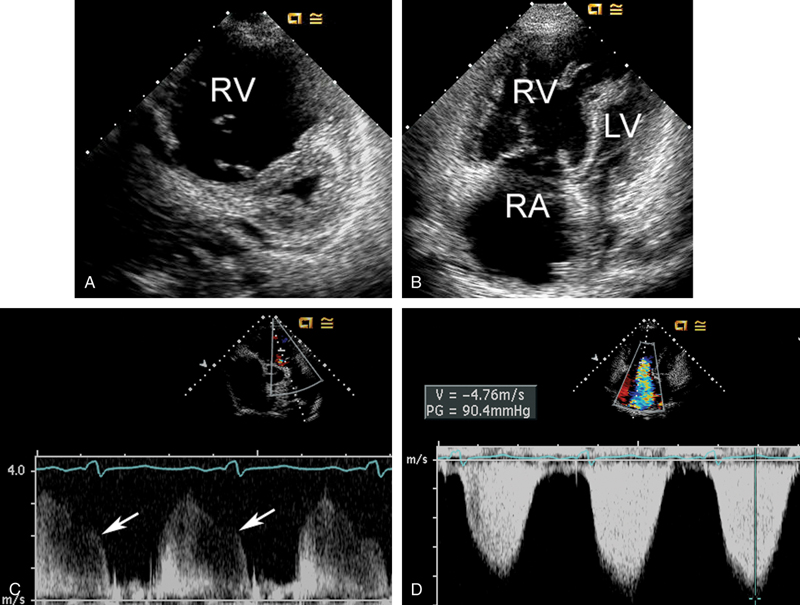

فحوصات تشخيصية لبعض امراض القلب والشرايين التاجية